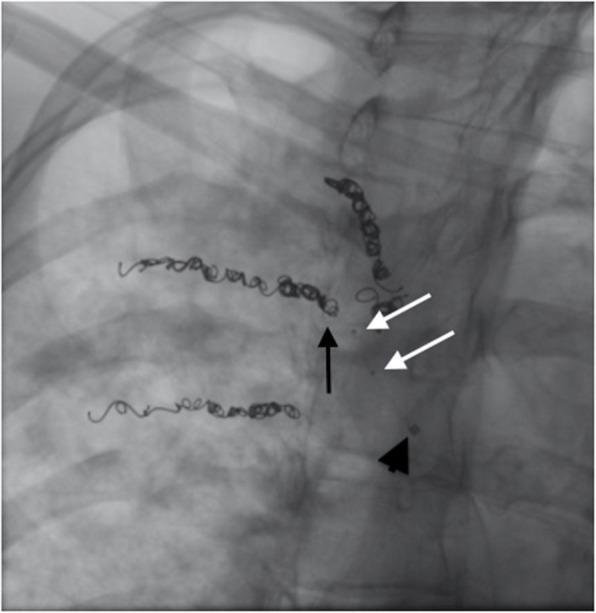

In this report, we describe a case of bronchial artery embolization of a complex Cystic Fibrosis patient with massive hemoptysis from recanalized coiled bronchial arteries utilizing a Scepter Balloon Catheter® (Microvention Terumo, USA) in administration of the liquid embolic agent Onyx® (Medtronic, USA).

The Scepter occlusion balloon catheter allowed for careful placement of the tip within the interstices of the pre-existing coils, allowing for Onyx injection directly into the coil mass without reflux, reconfirming the benefits of Onyx embolization in bronchial artery embolization and providing evidence that the Scepter occlusion balloon catheter should be added to the armamentarium of devices used in complex bronchial artery embolization for Cystic Fibrosis patients with massive hemoptysis.

在本报告中,我们描述了一例复杂囊性纤维化患者支气管动脉栓塞的病例,该患者因再通的盘绕支气管动脉出现大量咯血,我们使用Scepter球囊导管(美国Microvention Terumo公司)注入液体栓塞剂Onyx(美国美敦力公司)。

Scepter闭塞球囊导管能够将尖端小心地放置在原有线圈的间隙内,使Onyx能够直接注入线圈团块而无反流,再次证实了Onyx栓塞术在支气管动脉栓塞中的益处,并提供了证据表明应将Scepter闭塞球囊导管纳入用于患有大量咯血的囊性纤维化患者复杂支气管动脉栓塞的器械库中。